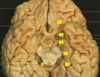

Brain regions for DBS

Which areas of the brain targeted for tremor? [3]

Which areas of the brain targeted for Dystonia? [1]

A

Tremor:

* Zona incerta

* Subthalamic nucleus

* GPin

Dystonia:

Which structures are the arrows pointing to? [5]